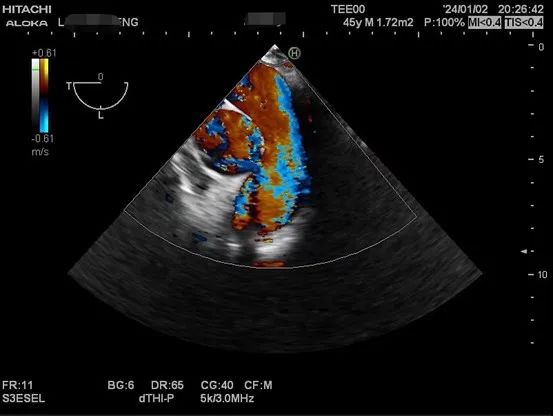

以下是肝移植术中TEE监测的图像。

肝硬化患者术前合并症较多,术中血流动力学波动剧烈,围术期可能发生严重低血压、心内血栓形成、肺栓塞、左室流出道梗阻、心室收缩舒张功能不全等危急事件,给麻醉管理带来巨大挑战。TEE是将超声探头放在食管中段或胃底,从心脏后方持续观察心脏结构和功能,避免肺气对成像的影响,图像清晰且不影响手术的操作,是肝移植术中重要的监测手段之一。美国心脏超声协会及美国心血管麻醉医师学会均推荐肝移植术中常规使用TEE。目前美国各大移植中心术中麻醉科术中常规使用TEE进行持续监测。